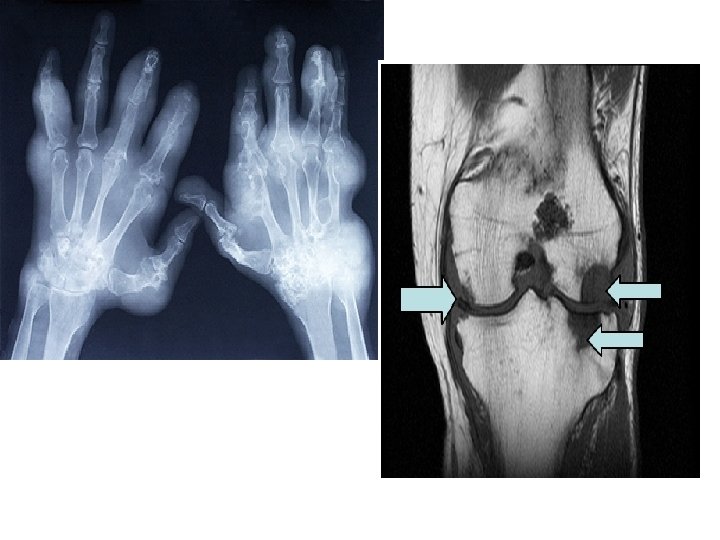

Arthritis

Gout • Gout is a disease that results from an overload of uric acid in the body. This overload of uric acid leads to the formation of tiny crystals of urate that deposit in tissues of the body, especially the joints. When crystals form in the joints it causes recurring attacks of joint inflammation (arthritis). Chronic gout can also lead to deposits of hard lumps of uric acid in and around the joints and may cause joint destruction, decreased kidney function, and kidney stones.